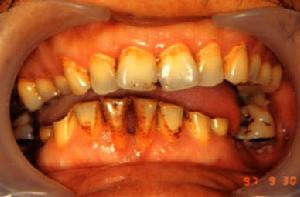

牙周萎縮多數成年人都患有牙周病,大多數牙周病進展緩慢,始發時多為牙周炎,除偶有刷牙出血外並無多少自覺症狀,所以不引人注意。而牙周炎發展到一定程度即為牙周炎,此時可出現嚴重口腔異味,牙周反覆膿腫,牙齒鬆動,牙縫越來越大,越來越稀疏,嚴重者牙齒脫落。患者若在此階段就診,醫生可以控制炎症惡化,但已破壞的牙周組織(包括牙周萎縮)是不可逆的,很難完全恢復。刷牙不當不正確的方法不但不能保護還會破壞牙齒及牙周組織,如過硬的牙刷、牙膏中摩擦劑顆粒過粗及拉鋸式刷牙,都可能導致牙周退縮。

不良修復體做得不好的假牙不易清潔,會導致牙周衛生不良,也會使牙周萎縮。當組織、器官或細胞成分在達到正常成熟之後,又減退、縮小,並失去其應有的功能稱為萎縮。牙周萎縮指的是全口廣泛的牙齒牙齦緣與牙槽骨同時退縮,使牙根暴露,但無明顯炎症和創傷者。其最常見的原因是牙周組織受到逐漸積累起來的各種損傷、刺激後造成的。

主要是齦緣部分存在異物又長期得不到清理,細菌滋生刺激長期存在所致;另外隨著年齡的增長也會或多或少發生萎縮,使牙根暴露,這種叫生理性萎縮,是不需治療的。再就是牙科手術不當留下的後遺症。保持清潔是延緩牙周萎縮的最有效的方法,定期洗牙亦顯得尤為重要。炎症性的牙周萎縮,主要表現為牙周紅腫脹痛,刷牙時常見出血。而老年牙周萎縮常使裸露了的牙極對冷熱的溫度變化及酸性食物等異常敏感,妨礙進食,降低生活質量,尢應注意防治。